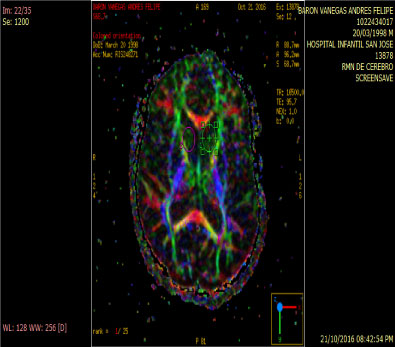

In people with schizophrenia regardless of whether or not they have been consuming cannabis an increase of rCB1 appears in area 9 of brodmann, whereas in cannabis users unrelated to the psychiatric diagnosis the increase of rCB1 is located in the area of the nucleus Caudate and put a men which are structures of the striatum [12] (Figure 3 and Figure 4).

Figure 3: Anitropic Map: ROI Caudate Nucleus. View Figure 3

Figure 4: Tractography: Abnormal by loss of connectivity between the cuadate nucleus and frontal lobe. View Figure 4